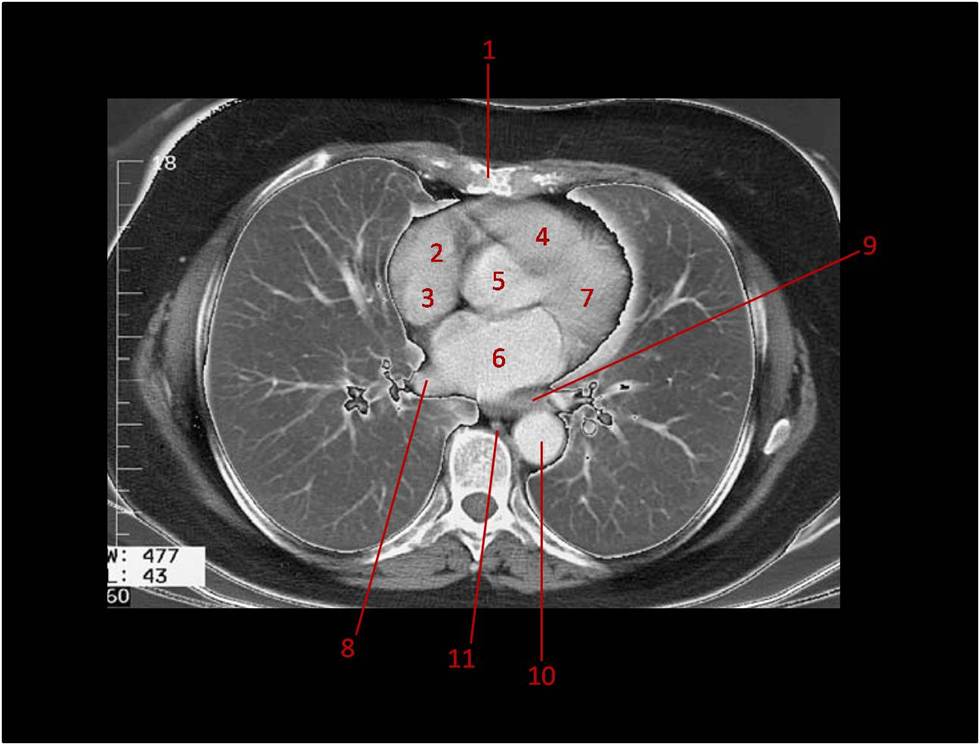

A imagem de tomografia computadorizada abaixo evidencia o mediastino médio (câmaras cardíacas e vasos da base):

1 - Corpo do osso esterno;

2 - Átrio direito;

3 - Veia cava superior. Desembocando na região posterior do átrio direito;

4 - Cone arterial. Início do tronco pulmonar, localizado na região de saída do ventrículo direito, superiormente a crista supraventricular;

5 - Parte ascendente da aorta. Local da valva aórtica, constituída por três válvulas semilunares (direita, esquerda e posterior). As válvulas semilunares direita e esquerda estão relacionadas com os óstios das respectivas artérias coronárias;

6 - Átrio esquerdo;

7 - Ventrículo esquerdo;

8 - Veia pulmonar direita;

9 - Veia pulmonar esquerda;

10 - Parte descendente torácica da aorta;

11 - Parte torácica do esôfago.